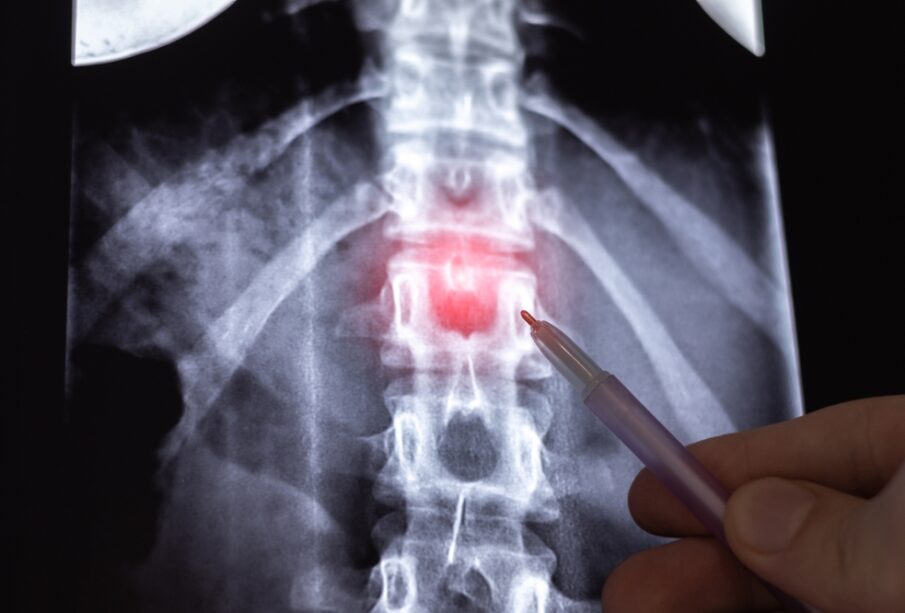

Užpakalinis disko išsigaubimas ir disko išvarža

Tarpuslankstelinio disko išsikišimas ir disko išvarža dažnai painiojami dėl jų panašių požymių, tačiau tai nėra tas pats sutrikimas. Nors abi būklės paveikia stuburo diskus, jų kilmė ir eiga skiriasi.

Iš pirmo žvilgsnio šie du sutrikimai atrodo panašūs, tačiau pagrindinis skirtumas glūdi tame, kur prasideda pažeidimas. Daugelis klaidingai mano, kad disko išsikišimas yra švelnesnė disko išvaržos forma, tačiau išsikišęs diskas – savarankiška būklė, kai diskas dar nesuplyšęs.

Išsikišimas atsiranda, kai disko centras – minkštas, drebučių konsistencijos branduolys – prasiplečia už įprastų ribų, bet vis dar lieka apsuptas tvirto išorinio sluoksnio. Šis sluoksnis, vadinamas žiediniu skaiduliniu apvalkalu, paprastai saugo vidinį turinį ir suteikia diskui atsparumo. Sveikame stubure šis žiedas sutampa su stuburo slankstelio kraštu, tačiau išsikišęs diskas peržengia šį rėžį.

Disko išvarža išsivysto tuomet, kai išorinis disko žiedas įplyšta ar suplyšta, ir dalis vidinio branduolio išteka už disko ribų. Tai dažnai sukelia uždegimą, skausmą ar spaudimą stuburo nervų šaknims.

Abi šios būklės – disko išsikišimas ir išvarža – turi savo ypatybes: išsikišimas įvyksta, kai diskas pakinta viduje, tačiau jo išorinės ribos lieka sveikos, tuo tarpu išvarža – kai plyšta ar įplyšta išorinis sluoksnis, leidžiantis vidiniam turiniui išeiti už disko ribų.